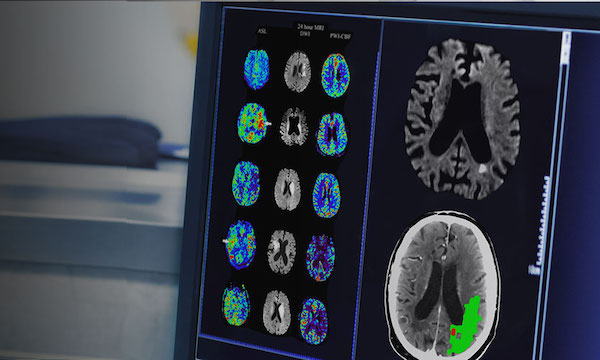

- Imaging and Radiation therapy

The Mark Hughes Foundation Centre for Brain Cancer Research is committed to finding a cure and improving the lives of those affected by brain cancer. We aim to advance brain cancer research and achieve the greatest impact for brain cancer patients and their families.